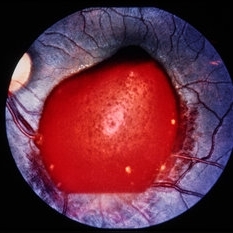

Pre-retinal and retinal hemorrhage with foreign body.

Condition/keywords: intraocular foreign body, trauma